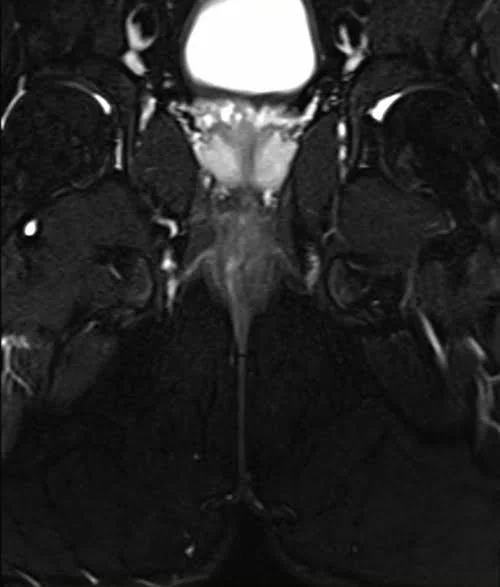

LUMBOSACRAL PLEXUS